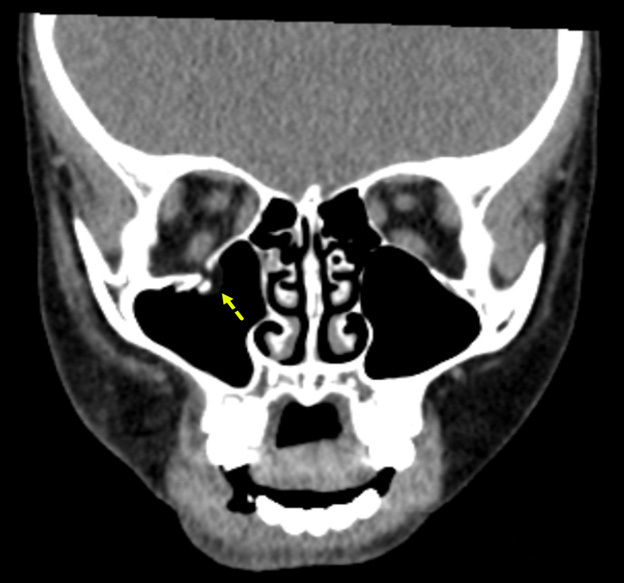

Figure 5 shows an example of an orbital floor fracture without evidence of entrapment in a pediatric patient in the coronal plane. In comparison, Figure 6 shows an entrapped orbital floor fracture in the bone window. The image reveals evidence of a non-displaced orbital fracture with entrapped intra-orbital fat.

Figure 5. Orbital Floor Fracture Without Evidence |

![]() |

The image shows a displaced orbital floor fracture with no evidence of entrapment. Image courtesy of Mantosh S. Rattan, MD, Radiologist, Orlando Health Arnold Palmer Children’s Hospital, Orlando, FL. |

Figure 6. Entrapped Orbital Floor Fracture |

The image shows evidence of a non-displaced orbital fracture with entrapped intra-orbital fat (bone window). Image courtesy of Mantosh S. Rattan, MD, Radiologist, Orlando Health Arnold Palmer Children’s Hospital, Orlando, FL. |